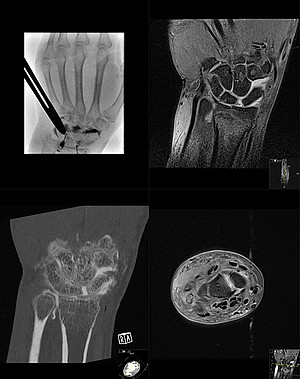

Wir bieten das gesamte Spektrum muskuloskelettaler Diagnostik und interventioneller Therapie. Dabei kommen sowohl etablierte Anwendungen auf dem neuesten technischen und wissenschaftlichen Stand als auch innovative und zukunftsorientierte Verfahren zum Einsatz. Diese beinhalten die konventionelle Radiographie (klassisches Röntgenbild), Ultraschall, Computertomografie (CT), Magnetresonanztomographie (MRT), Arthrographie und bildgebungsgesteuerte Punktionen.

• MR- und CT-Arthrographie